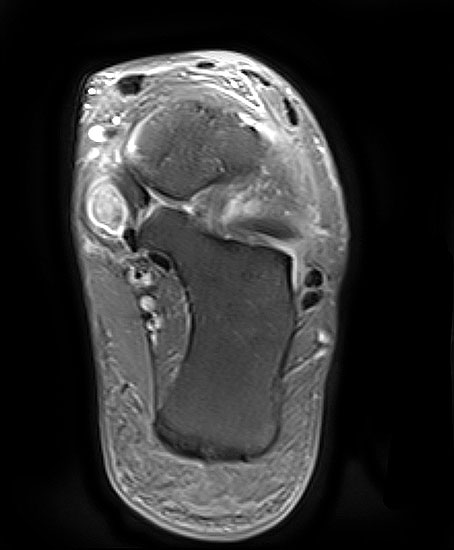

Rupturierte Tibialis posterior Sehne in den coronaren, protonensensitiven Schichten. Bei diskreten Läsionen erhöht die Gabe von Kontrastmittel die Beurteilbarkeit.

Abbildung 6g

Die Magnet-Resonanz-Tomographie (MRT) eignet sich besonders zur Darstellung der Tenosynovitis und Degeneration der Tibialis posterior Sehne. Hinsichtlich Sensitivität und Spezifität ist das MRT dem CT insbesondere bei Sehnenlängsrupturen überlegen 23. Die normale Sehne erscheint auf dem MRT mit schwarzem, homogenem Signal und ovaler Form, zwei bis dreimal dicker als die Sehne des M. flexor digitorum longus. Ein schmaler Flüssigkeitsaum < 1-2 mm ist physiologisch. Bei der Tenosynovitis ist der Saum deutlich breiter und neben dem Ödem in der Sehnenmatrix am besten auf den T2-Wichtungen zu erkennen. Strukturelle Veränderungen der Sehnenmatrix, wie z.B. Partial- oder Längsrupturen sind besser auf den T1-Wichtungen zu sehen. Nach der Sehnenhypertrophie im Stadium I der Erkrankung kommt es jeweils mit wenig oder keiner Begleitentzündung im Stadium II zur Elongation und Abnahme des Sehnendurchmessers und im Stadium III zur Ruptur, welche im MRT gut ersichtlich sind. Hingegen finden sich mit zunehmender Dauer der Erkrankung Entzündungszeichen infolge fibulocalcanearen Impingements und lateral betonter OSG-Degeneration und Arthrose v.a. auf den T2-Wichtungen.